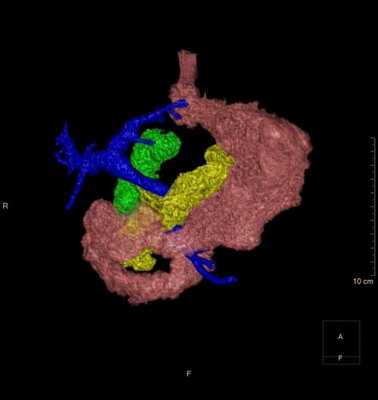

Риски и особенности ситуации

К особенностям ситуации нужно отнести крупный размер и сложную конфигурацию кисты, ее преимущественно внеорганное расположение и близость воротной вены. Для того чтобы оценить пространственное соотношение кисты с прилежащими анатомическими структурами, а также определить наилучшее место для дренирования, была проведена 3D виртуальная компьютерная реконструкция (рис. 4).

Рис. 4